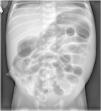

Se presenta el caso de gemelos nacidos de una gestación monocorial biamniótica, a término (37+1 semanas), de 2.300 y 2.490g de peso, respectivamente, sin antecedentes de interés. Fueron ingresados con 27h de vida por retraso en la eliminación de meconio con importante distensión abdominal, mala coloración y aspecto séptico. En la radiografía abdominal se observa dilatación de asas intestinales (fig. 1). Tras la administración de enema de N-acetilcisteína 10% expulsan un cordón meconial viscoso donde se observa la impronta de haustras colónicas (fig. 2). Presentan mejoría progresiva con buen tránsito intestinal y sin presentar vómitos. Se descartó la existencia de enfermedades asociadas3. No han vuelto a presentar episodios de obstrucción intestinal.